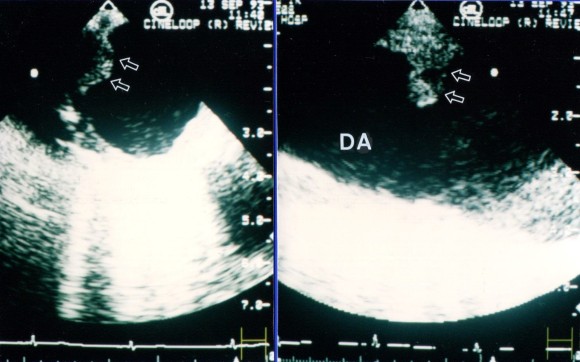

흉부하행 대동맥의 이면성 심애코-좌측은 단축상 1012시 방향으로 동맥경화반을 볼 수 있다.오른쪽은 장축상으로 막대 모양의 동맥경화반이 보인다.